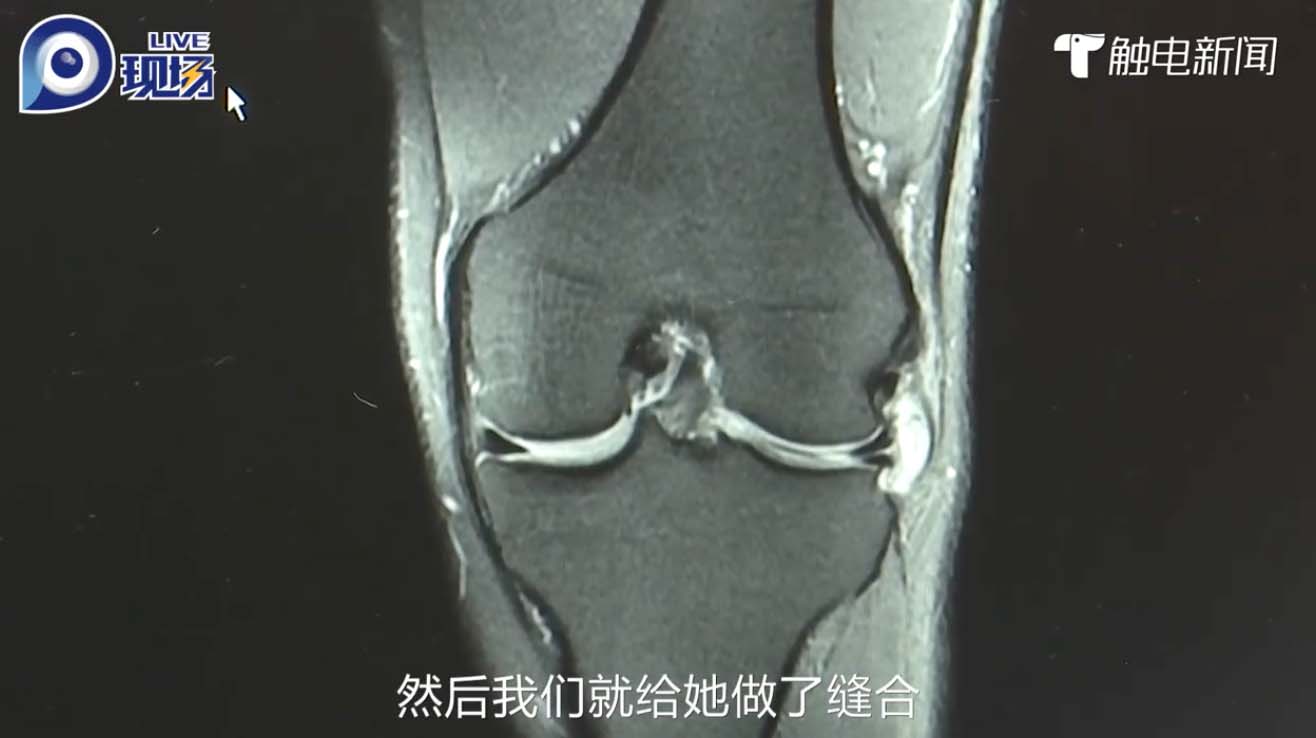

眾所週知,節食減肥絕對會危害健康,大家應該追求健康美,以正確方式減重,例如做運動。然而,過量運動亦有可能危害健康,所以要適可而止!近日,內地一名女子為了減肥,於是每天在家跳繩5000下,不料一週後膝蓋就出現疼痛,後來更無法走路,需要坐輪椅求醫。經檢查後,醫生診斷她患有半月板受損,或因與過度運動有關。

根據內地媒體《觸電新聞》報導指,內地珠海一名黃姓女子為了減肥,於是決定每天跳繩,由剛開始每天跳1000下,後來逐步每天增至跳5000下,其身形確實有明顯變化。不過,她的膝蓋同時亦出現疼痛不適等症狀,但黃女士並未有多加留意。直至她的疼痛痛楚無法忍受,更不能正常走路需要坐輪椅,其家人就將她推到醫院求醫。經詳細檢查後,醫生診斷黃女士患有半月板嚴重損傷。幸好經過適當治療後並沒有大礙。

鄭州大學附屬鄭州中心醫院關節與運動損傷病區住院醫生朱征威解釋,不正確的跳繩動作方式對膝蓋,腳踝影響甚大,而且經常重複的做一個動作都可能對半月板造成損傷。